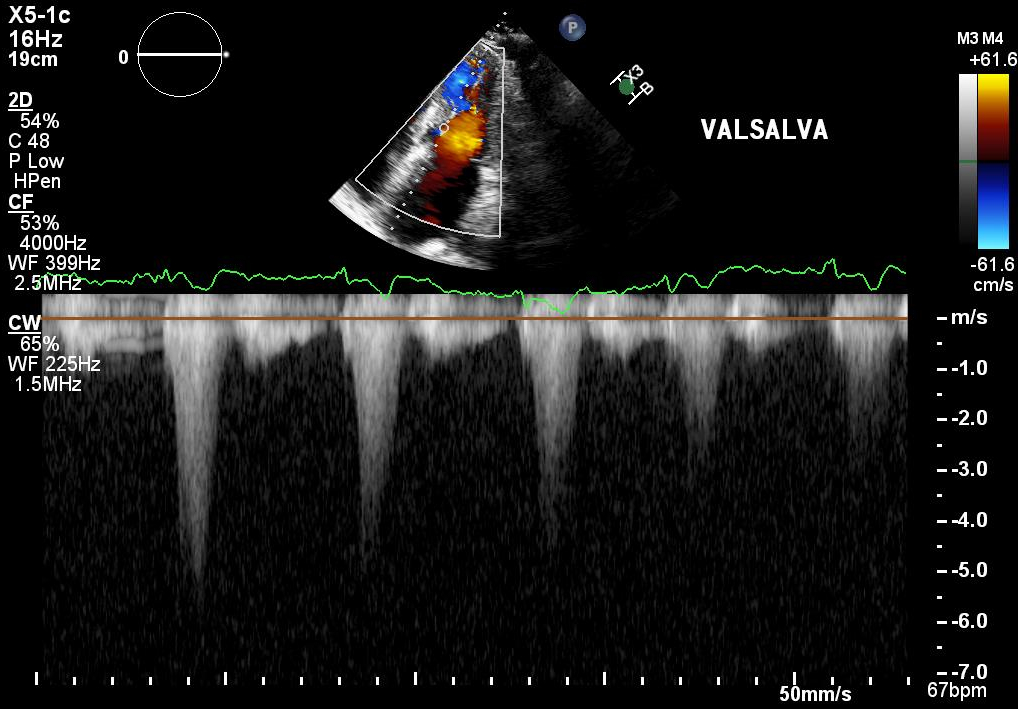

12 weeks after initiation of mavacamten, surveillance TTE demonstrated a LVOT gradient of 7 mmHg at rest and 11 mmHg during Valsalva maneuver, and a basal septal wall thickness of 1.0 cm. Severe mitral regurgitation was noted with the mechanism identified as both Carpentier type I and II. The primary etiology of the regurgitation was determined to be P3 prolapse (Figure 2). There was no longer evidence of SAM.

The patient remained symptomatic and was referred to cardiothoracic surgery for mitral transcatheter edge-to-edge repair (mTEER). Post procedure, the patient’s dyspnea resolved. TTE showed the implanted Mitraclip with trace intra-valvular mitral regurgitation (Figure 3).